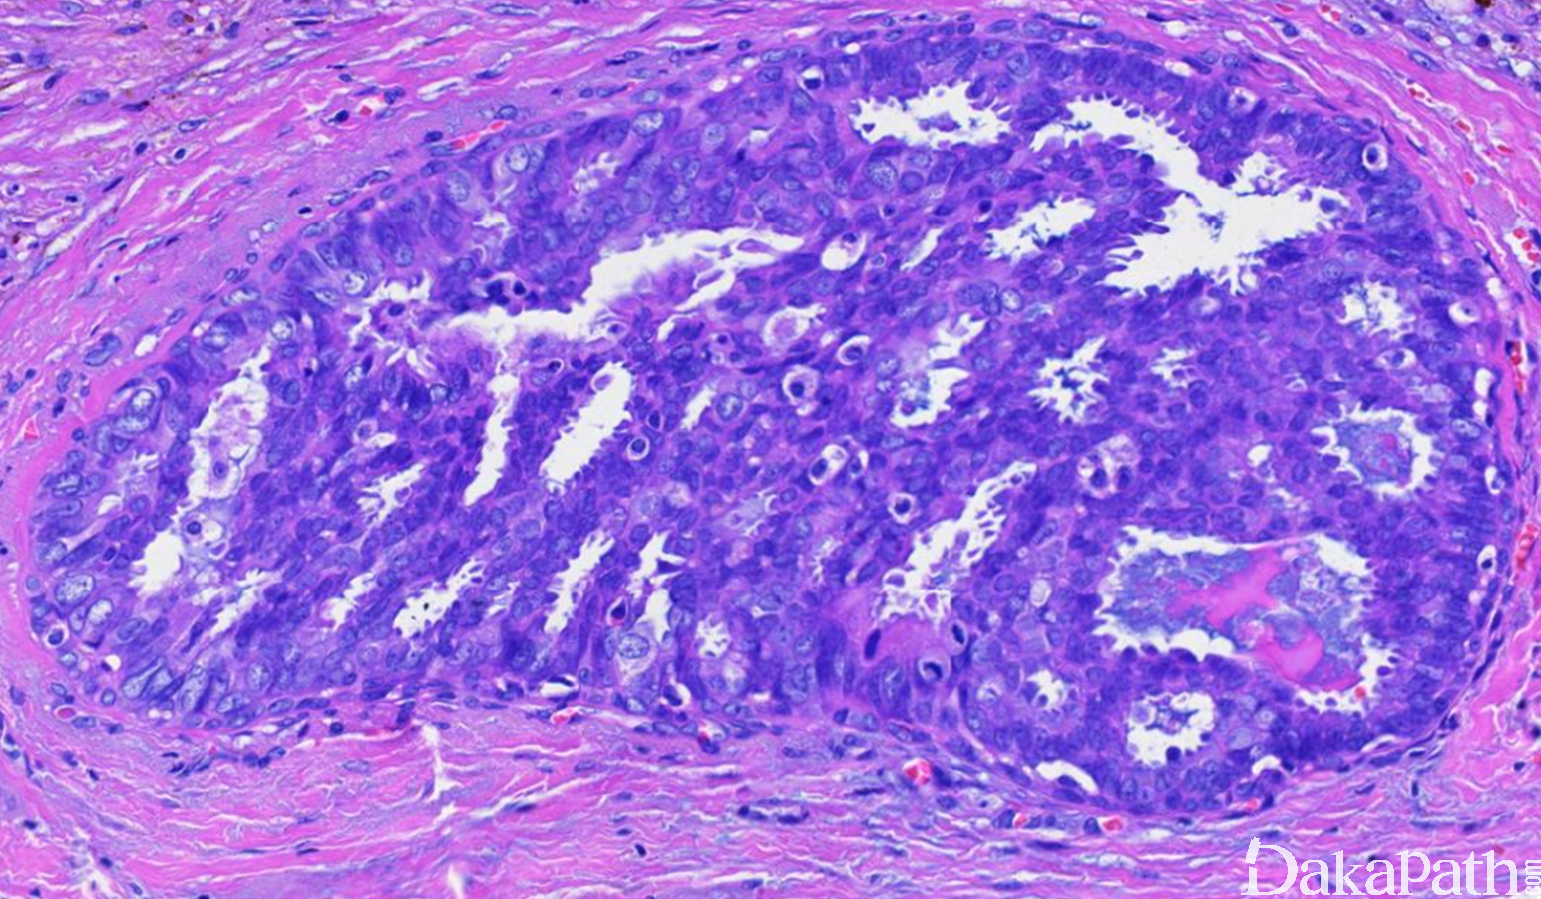

导管原位癌导管囊性扩张,腔内充满嗜酸性分泌物,为原位癌的一种少见亚型,可发展为浸润癌。

导管原位癌背景,常为微乳头型;

导管扩张,囊性,腔内充满嗜酸性分泌物,似甲状腺胶体,周边可有收缩缝隙

细胞顶端可见鞋钉样分泌物,低级别核;

分泌物可外渗浸润间质,但不能认为是浸润;